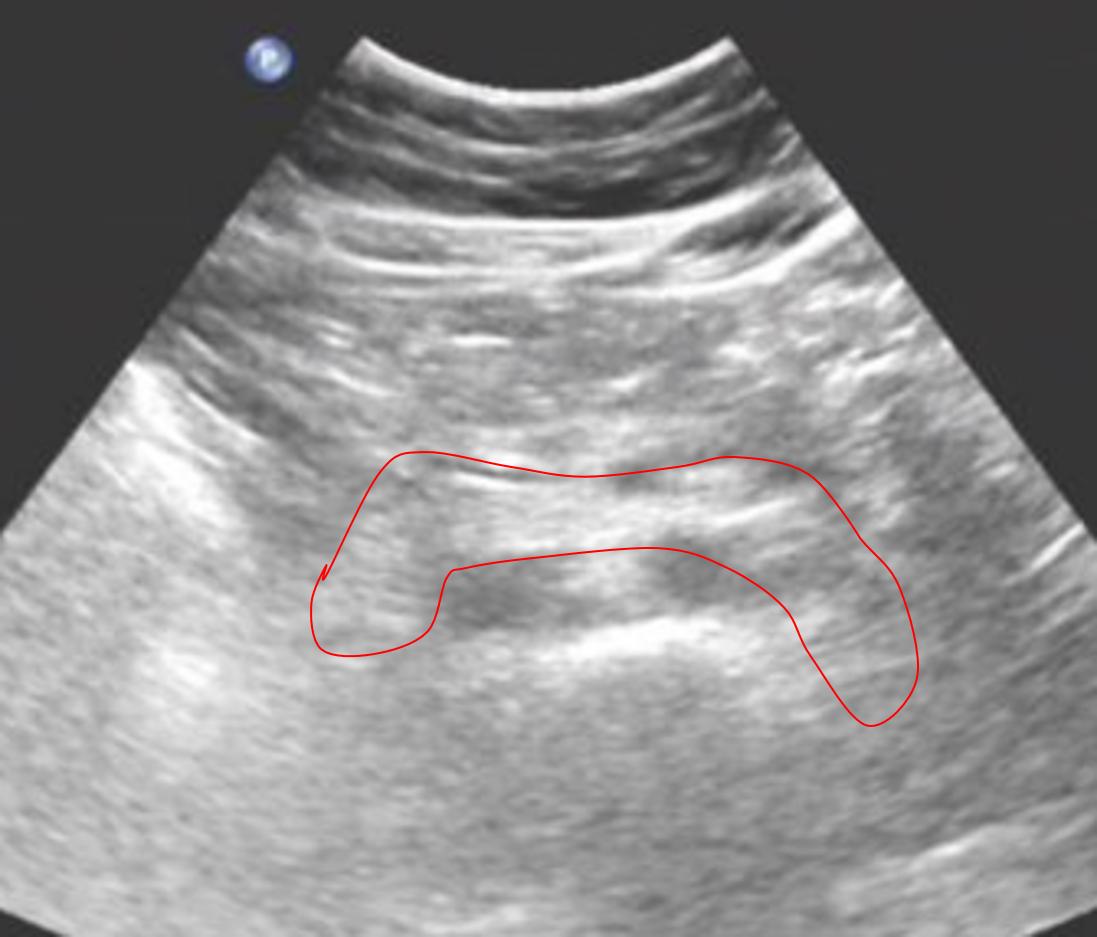

对于腹彩超声医生来说,最大的敌人可能就是胃肠道内的气体了,超声照射在气体上,会形成一团白白亮亮的“高回声”,这像云朵的一团“高回声”遮挡住了后方的器官,无法显示出来。所以对于一些餐后的患者,由于胃内的食物残渣和气体的遮挡,后面的胰腺很多时候就无法显示。

图一,餐后的上腹部,中间这团白白的亮亮的“云朵”就是气体,后面的脏器被气体的“光芒”所遮挡,完全无法显示,这个时候患者有胰腺炎,胰腺的肿瘤,就无法显示出来了。

图二,空腹的患者,红线圈出来的部分就是胰腺,可以看到这个胰腺回声均匀,并且没有长东西,是一个健康的胰腺~